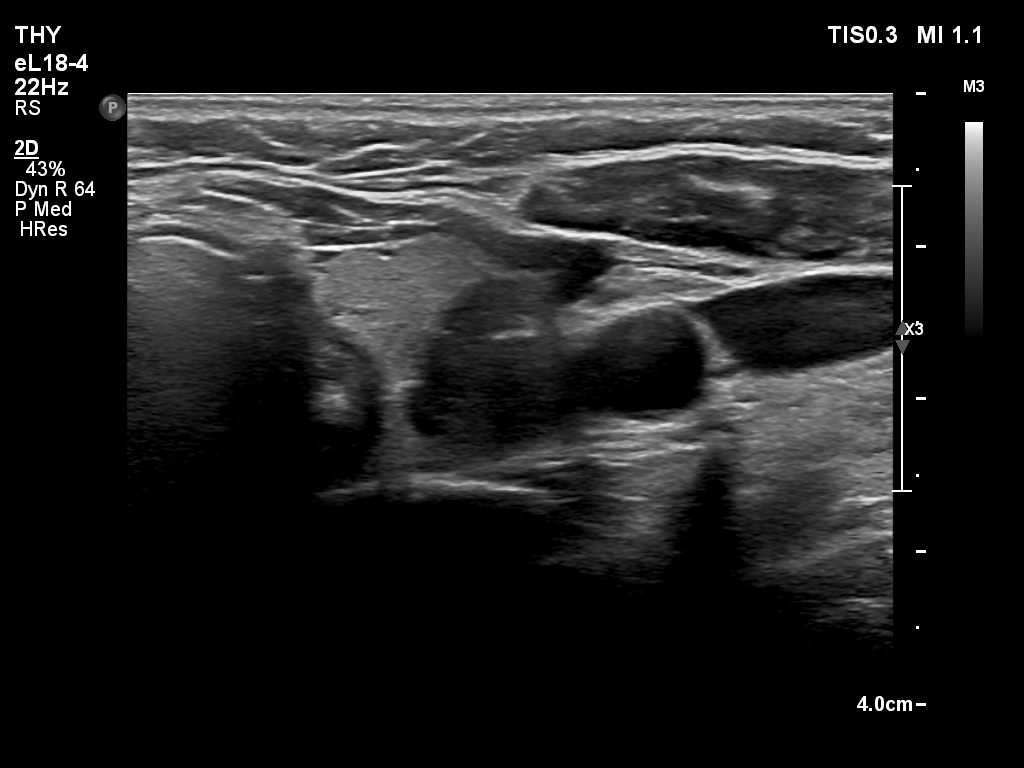

Ultrasonography. The thyroid was echonormal and had multiple nodules. There were cystic areas, an almost completely cystic nodule, and a dominantly solid nodule in the right lobe. The left lobe had three lesions. The upper solid lesion was the one we treated 16 years ago. The middle lesion was a dominantly solid while the lower one seemed to be a pure cyst. The dimensions of the nodule which has been treated with sclerotherapy were 10x11x13 mm (width, depth and length, respectively). There was a large cystic nodule in the upper pole of the left lobe. The lesion showed relatively large hyperechogenic granules. There were multiple enlarged lymph nodes lateral to the left lobe, two of largest were cystic.

After removing 4 mL fluid from the lowest lesion in the left lobe, the lesion has disappeared, which proves that this was a pure cyst. Cytology resulted in cystic degeneration.